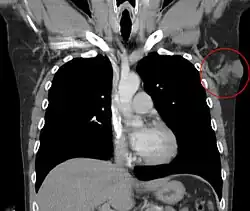

Ze względu na stosunkowo rzadką obecność przerzutów nie wymaga się rutynowego wykonywania szerokiej diagnostyki obrazowej w celu oceny zaawansowania choroby, chyba że wywiad, badanie fizykalne lub stwierdzone niekorzystne czynniki ryzyka przemawiają za koniecznością poszerzenia diagnostyki[4][25][8]. Niektórzy autorzy w przypadku bardzo rozległej i zaawansowanej miejscowo choroby zalecają wykonanie tomografii komputerowej klatki piersiowej w celu wykluczenia rozsiewu do płuc, choć zwykle wystarczające jest wykonanie zdjęcia rentgenowskiego klatki piersiowej[8][13].